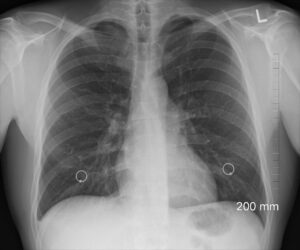

Asimismo, apunta que la mayoría ha padecido cuadros respiratorios agudos, como bronquitis, enfermedad que tiene síntomas similares a la neumonía, es decir, tos, flemas, fiebre o malestar. La diferencia la hace el diagnóstico de esta última, que además de clínico, es radiológico: una radiografía de tórax muestra una mancha blanca en el pulmón del paciente, la cual significa que esa zona está inflamada debido a la infección. Dicha alteración puede registrarse en una pequeña área, la mitad o en todo el órgano, o en ambos pulmones.